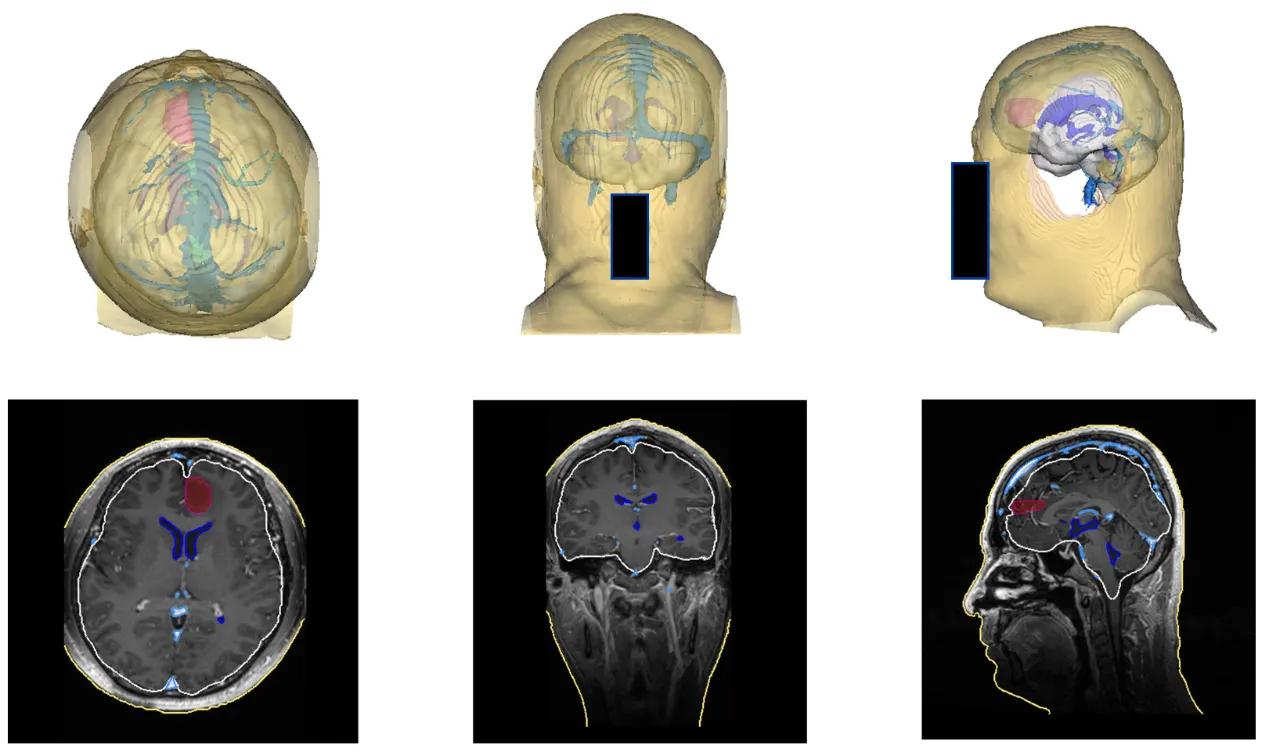

术前,基于AI和影像技术,该手术导航系统能够将磁共振、CT等影像自动进行分割重建及三维可视化处理,通过腾讯AI Lab的算法能力,一键生成定制化的3D“透明脑”,方便医生制定手术计划,向病人和家属讲解手术方案。

(术前“透明脑”生成)